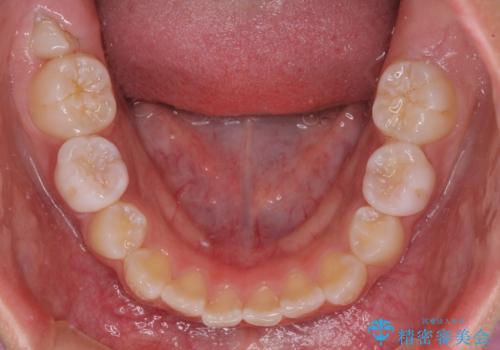

- 小学校での定期歯科検診にて歯列不正を指摘されたとのことで来院された患者様です。

左上の犬歯が低位に埋伏しており、将来八重歯になるリスクが高いと判断されたため、補助装置とワイヤーを用いて犬歯を通常の位置まで移動させることとしました。

今後残っている乳歯が抜け、永久歯が萌出してくるため、調整可能なリンガルアーチを用いて保定を行っています。

12歳臼歯が萌出するまで経過観察を行い、すべての歯が萌出した後に、全顎矯正治療(Ⅱ期治療)を行っていきます。